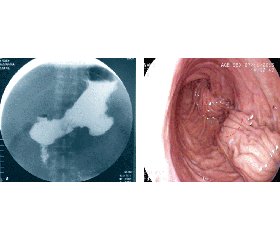

Для дифференцировки этих двух принципиально различных состояний использовали фиброгастродуоденоскопию. При отеке слизистой оболочки, несмотря на полное прилегание инвагинированной складки к внутренним поверхностям стенок желудка, отсутствие единого непрерывного канала вдоль всей длины желудка, фиброгастроскоп с небольшим усилием проходит в двенадцатиперстную кишку. Поэтому в данных 8 случаях устанавливали назогастроинтестинальный зонд для энтерального питания, проводили консервативную противовоспалительную, противоотечную терапию. В последующем для профилактики этих состояний разработали и использовали следующие мероприятия: при операции ушивание стенок желудка проводили без натяжения, с формированием единого просветного канала, с применением желудочного зонда размером 12 мм (36 Fr). Разработанная и внедренная собственная модификация методики гастропликации способствует формированию и сохранению канала вдоль малой кривизны желудка, предотвращает явления динамической непроходимости.

По методике М. Talebpour инвагинированная стенка желудка сгибается, формируя небольшие полости, которые нарушают пассаж даже жидкого содержимого. Наличие нескольких узких каналов также затрудняет проведение фиброгастроскопии при дифференцировке динамической и анатомической непроходимости.

Сущность модифицированной методики (рис. 2) заключается в том, что во время ушивания стенок желудка не только сшиваются передняя и задняя его стенки, но также вовлекается большая кривизна желудка. Первый шов накладывается на заднюю стенку желудка, второй — на линию мобилизации сальника в области большой кривизны, третий — на переднюю стенку желудка, что способствует формированию единого целостного канала вдоль малой кривизны, через который может проходить жидкость и пища.

В этом случае возможно проведение ранней фиброгастроскопии, позволяющей своевременно решить вопрос о необходимости реоперативного вмешательства при функциональном процессе вследствие отека слизистой оболочки.

Более редкими осложнениями были: псевдодивертикул зоны пликации в области тела желудка, расширение области дна желудка, стеноз (стриктура) области угла желудка, депликация желудка (рис. 3).